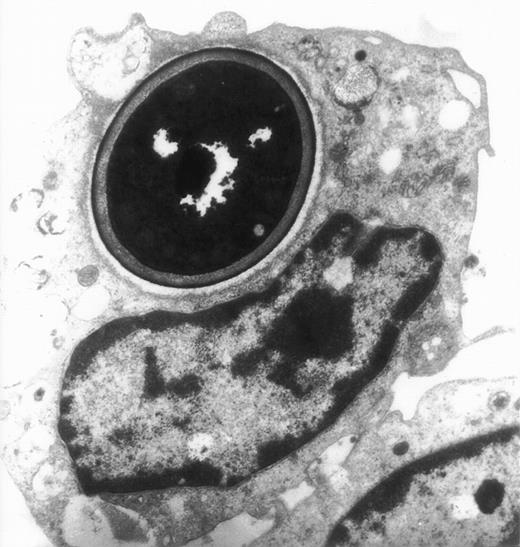

The actin network plays a major role in chemotaxis and phagocytosis. To study the effects of jaspamide on phagocytosis, HL-60 cells and monocytes were exposed for 24 hours to 10−7 mol/L jaspamide, incubated with C albicans for 60 minutes, and examined for phagocytosis. Jaspamide did not affect the percentage of phagocytosing cells or the number of yeast particles phagocytosed by each cell (Table 3). To ascertain that aggregated actin clusters did not affect phagocytosis, fluorescein-labeled C albicans was incubated with jaspamide-treated HL-60 cells and monocytes. The cells were fixed, Rh-phalloidin stained, and analyzed by CLSM. HL-60 cells (Fig 6A and C [see page 3998]) and human monocytes (Fig 6B and D [see page 3998]) that show jaspamide-induced actin aggregates phagocytose C albicans. Electron microscopy analysis of jaspamide-treated monocytes incubated with C albicans shows that the C albicans was phagocytosed and is located inside the cell (Fig 7).

Electron migrograph of a monocyte that phagocytosed C albicans. A thin section through monocytes following their growth for 24 hours in the presence of 10−7 mol/L jaspamide and their exposure for 30 minutes to C albicans (original magnification × 9,250).